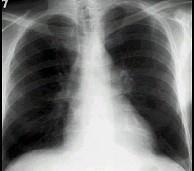

问题 女性,55岁,慢性咳嗽、咳痰、气喘,15年。肘静脉压20cmH0。胸部X线见图。最可能的诊断是 ( )

选项 A.原发性肺动脉高压症 B.房间隔缺损 C.原发性肌病 D.慢性肺源性心脏病 E.以上均不是

答案 D